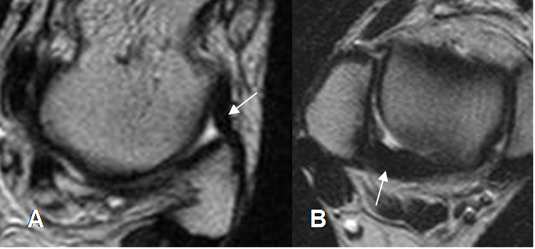

Fig 65 B. Lesión ligamentaria crónica.

A: RM coronal en T1. Pérdida de la señal normal de los ligamentos peroneoastragalino posterior (Flecha delgada) y peroneocalcaneo (Flecha gruesa).

B: RM axial en T2 y C: RM axial en T1. Los componentes del ligamento colateral lateral están engrosados y con alteración de su señal, por lesión crónica.